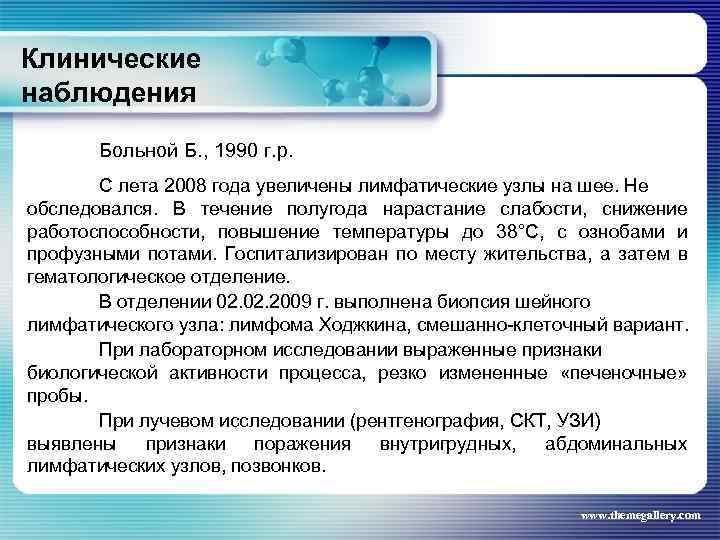

Клинические наблюдения Больной Б. , 1990 г. р. С лета 2008 года увеличены лимфатические узлы на шее. Не обследовался. В течение полугода нарастание слабости, снижение работоспособности, повышение температуры до 38°С, с ознобами и профузными потами. Госпитализирован по месту жительства, а затем в гематологическое отделение. В отделении 02. 2009 г. выполнена биопсия шейного лимфатического узла: лимфома Ходжкина, смешанно-клеточный вариант. При лабораторном исследовании выраженные признаки биологической активности процесса, резко измененные «печеночные» пробы. При лучевом исследовании (рентгенография, СКТ, УЗИ) выявлены признаки поражения внутригрудных, абдоминальных лимфатических узлов, позвонков. www. themegallery. com

Клинические наблюдения Больной Б. , 1990 г. р. С лета 2008 года увеличены лимфатические узлы на шее. Не обследовался. В течение полугода нарастание слабости, снижение работоспособности, повышение температуры до 38°С, с ознобами и профузными потами. Госпитализирован по месту жительства, а затем в гематологическое отделение. В отделении 02. 2009 г. выполнена биопсия шейного лимфатического узла: лимфома Ходжкина, смешанно-клеточный вариант. При лабораторном исследовании выраженные признаки биологической активности процесса, резко измененные «печеночные» пробы. При лучевом исследовании (рентгенография, СКТ, УЗИ) выявлены признаки поражения внутригрудных, абдоминальных лимфатических узлов, позвонков. www. themegallery. com

Клинические наблюдения Тот же пациент Был сформулирован клинический диагноз: Лифома Ходжкина, нодулярный склероз IV B стадия с поражением шейных, надключичных, подчелюстных, подмышечных, переднегрудных, парастернальных, паховых, внутригрудных, абдоминальных лимфатических узлов, печени, костного мозга, позвонков. В связи с выраженной нарастающей интоксикацией была начата терапия преднизолоном и первый цикл ВЕАСОРР. на этом фоне появились: резко повышенные показатели трансаминаз, асцит, массивные белковые отёки, сохранилась опухолевая интоксикация. Развилась аплазия гемопоеза. Доза преднизолона была увеличена. На этом фоне развилась полисегментарная грибковая пневмония. www. themegallery. com

Клинические наблюдения Тот же пациент Был сформулирован клинический диагноз: Лифома Ходжкина, нодулярный склероз IV B стадия с поражением шейных, надключичных, подчелюстных, подмышечных, переднегрудных, парастернальных, паховых, внутригрудных, абдоминальных лимфатических узлов, печени, костного мозга, позвонков. В связи с выраженной нарастающей интоксикацией была начата терапия преднизолоном и первый цикл ВЕАСОРР. на этом фоне появились: резко повышенные показатели трансаминаз, асцит, массивные белковые отёки, сохранилась опухолевая интоксикация. Развилась аплазия гемопоеза. Доза преднизолона была увеличена. На этом фоне развилась полисегментарная грибковая пневмония. www. themegallery. com